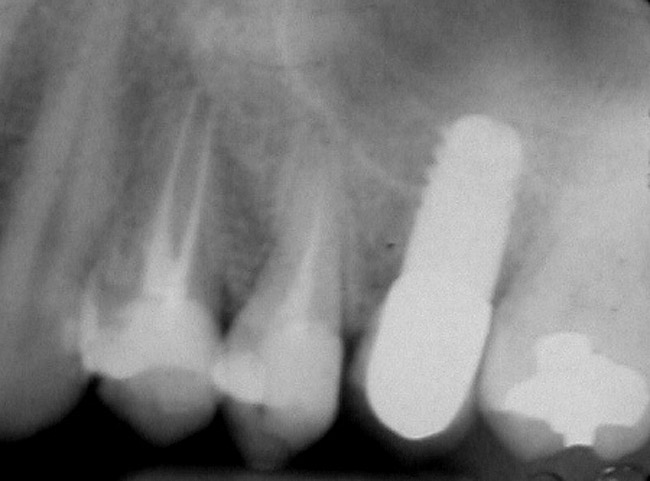

Case 2

A 55-year-old male was referred for implant placement and prosthetic rehabilitation in the area of tooth No. 15. The tooth had been extracted 4 years prior. The radiograph revealed inadequate bone height for implant positioning (Figure 6). It was decided to insert an implant that was 11.5 mm in length and 3.75 mm in diameter, performing a slight osteotomic maxillary sinus lift. A heterologous bone graft also was planned to obtain a larger sinus lift.

A full-thickness mucoperiosteal flap was raised, and alternating osteotomes were used to prepare the implant site. After achieving a length of 7 mm (Figure 7A and Figure 7B), heterologous bone graft was implanted and the osteotome sequence was repeated. The implant showed primary stability.

Figure 6  Preoperative radiograph of the area around tooth No. 15.

Figure 6